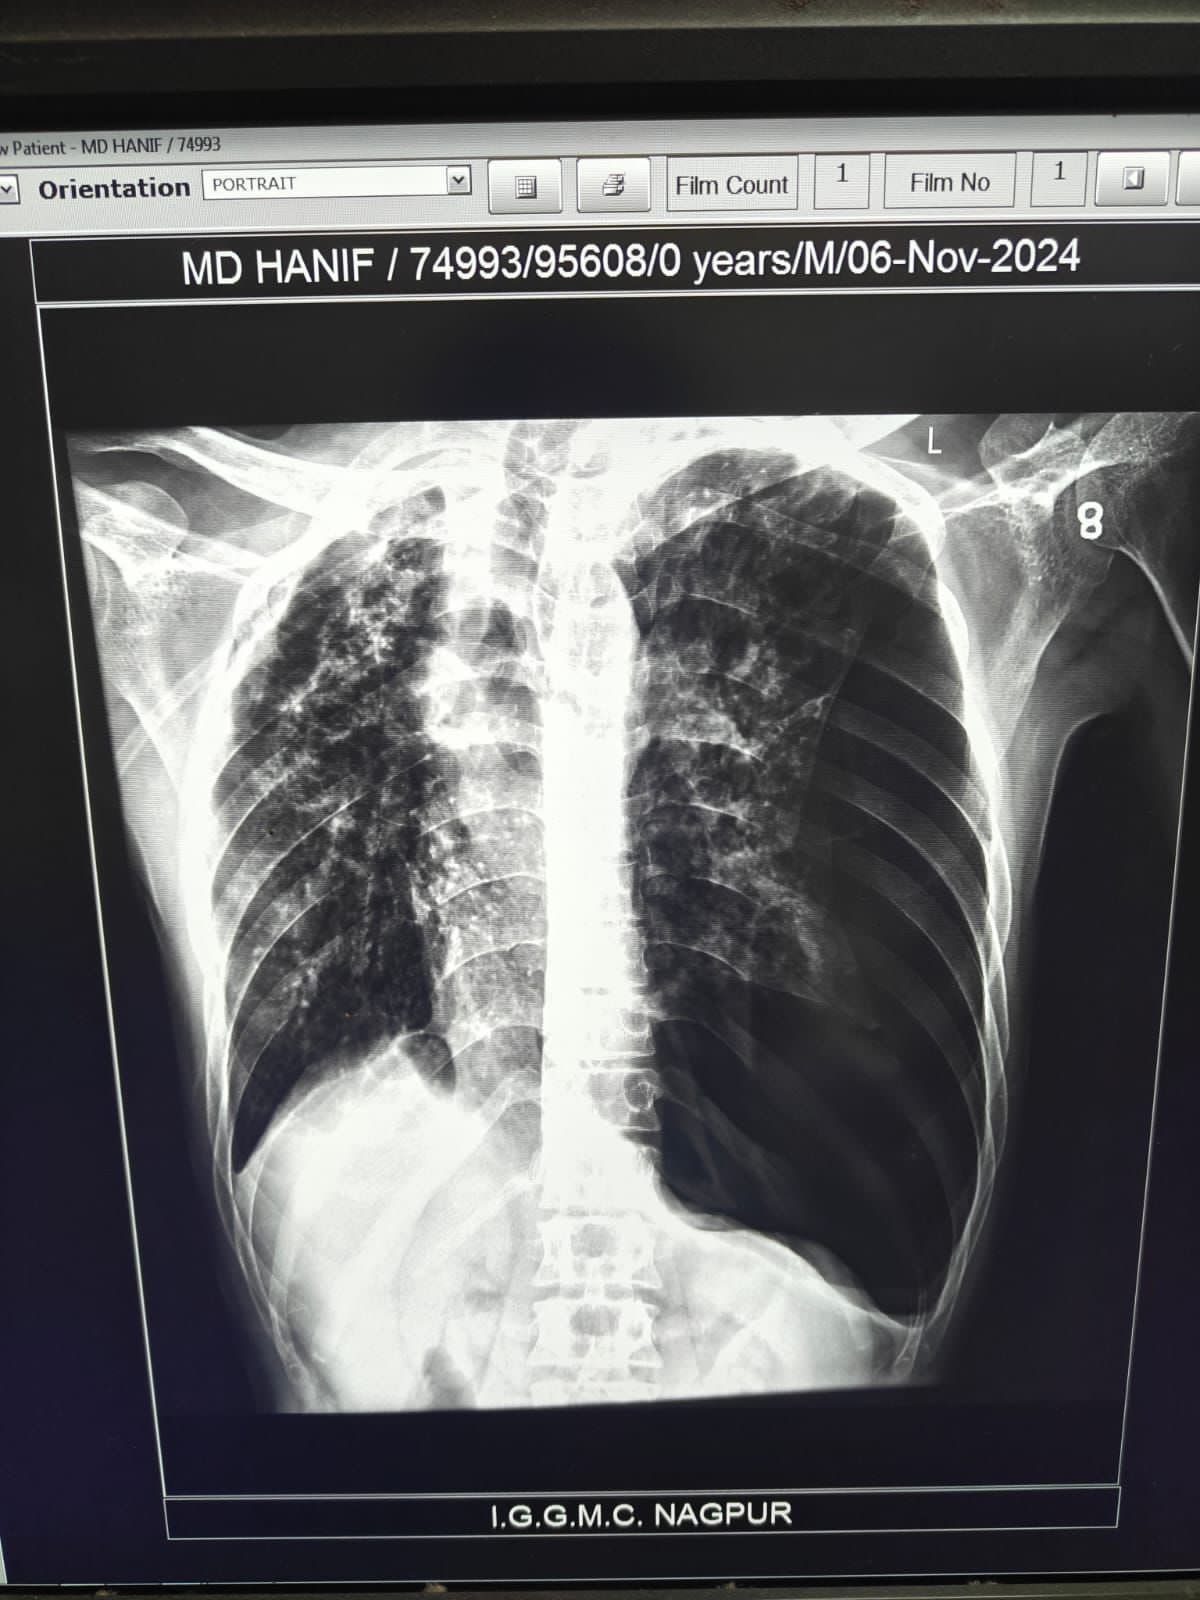

| 205 | IGGMC, Nagpur, Nagpur | P2 | 29-4267 | MOHAMMAD HANIF SUREYYA | Consent taken on Paper | 55 Yrs. |

Provisional Diag : PTB?

Final Diag : PNAEMOTHORAX /CLINICALLY DIAGNOSED PTB |

TB Case (Confirmed) | LEFT SIDED PNAEMOTHORAX | Abnormality visible on x-ray |